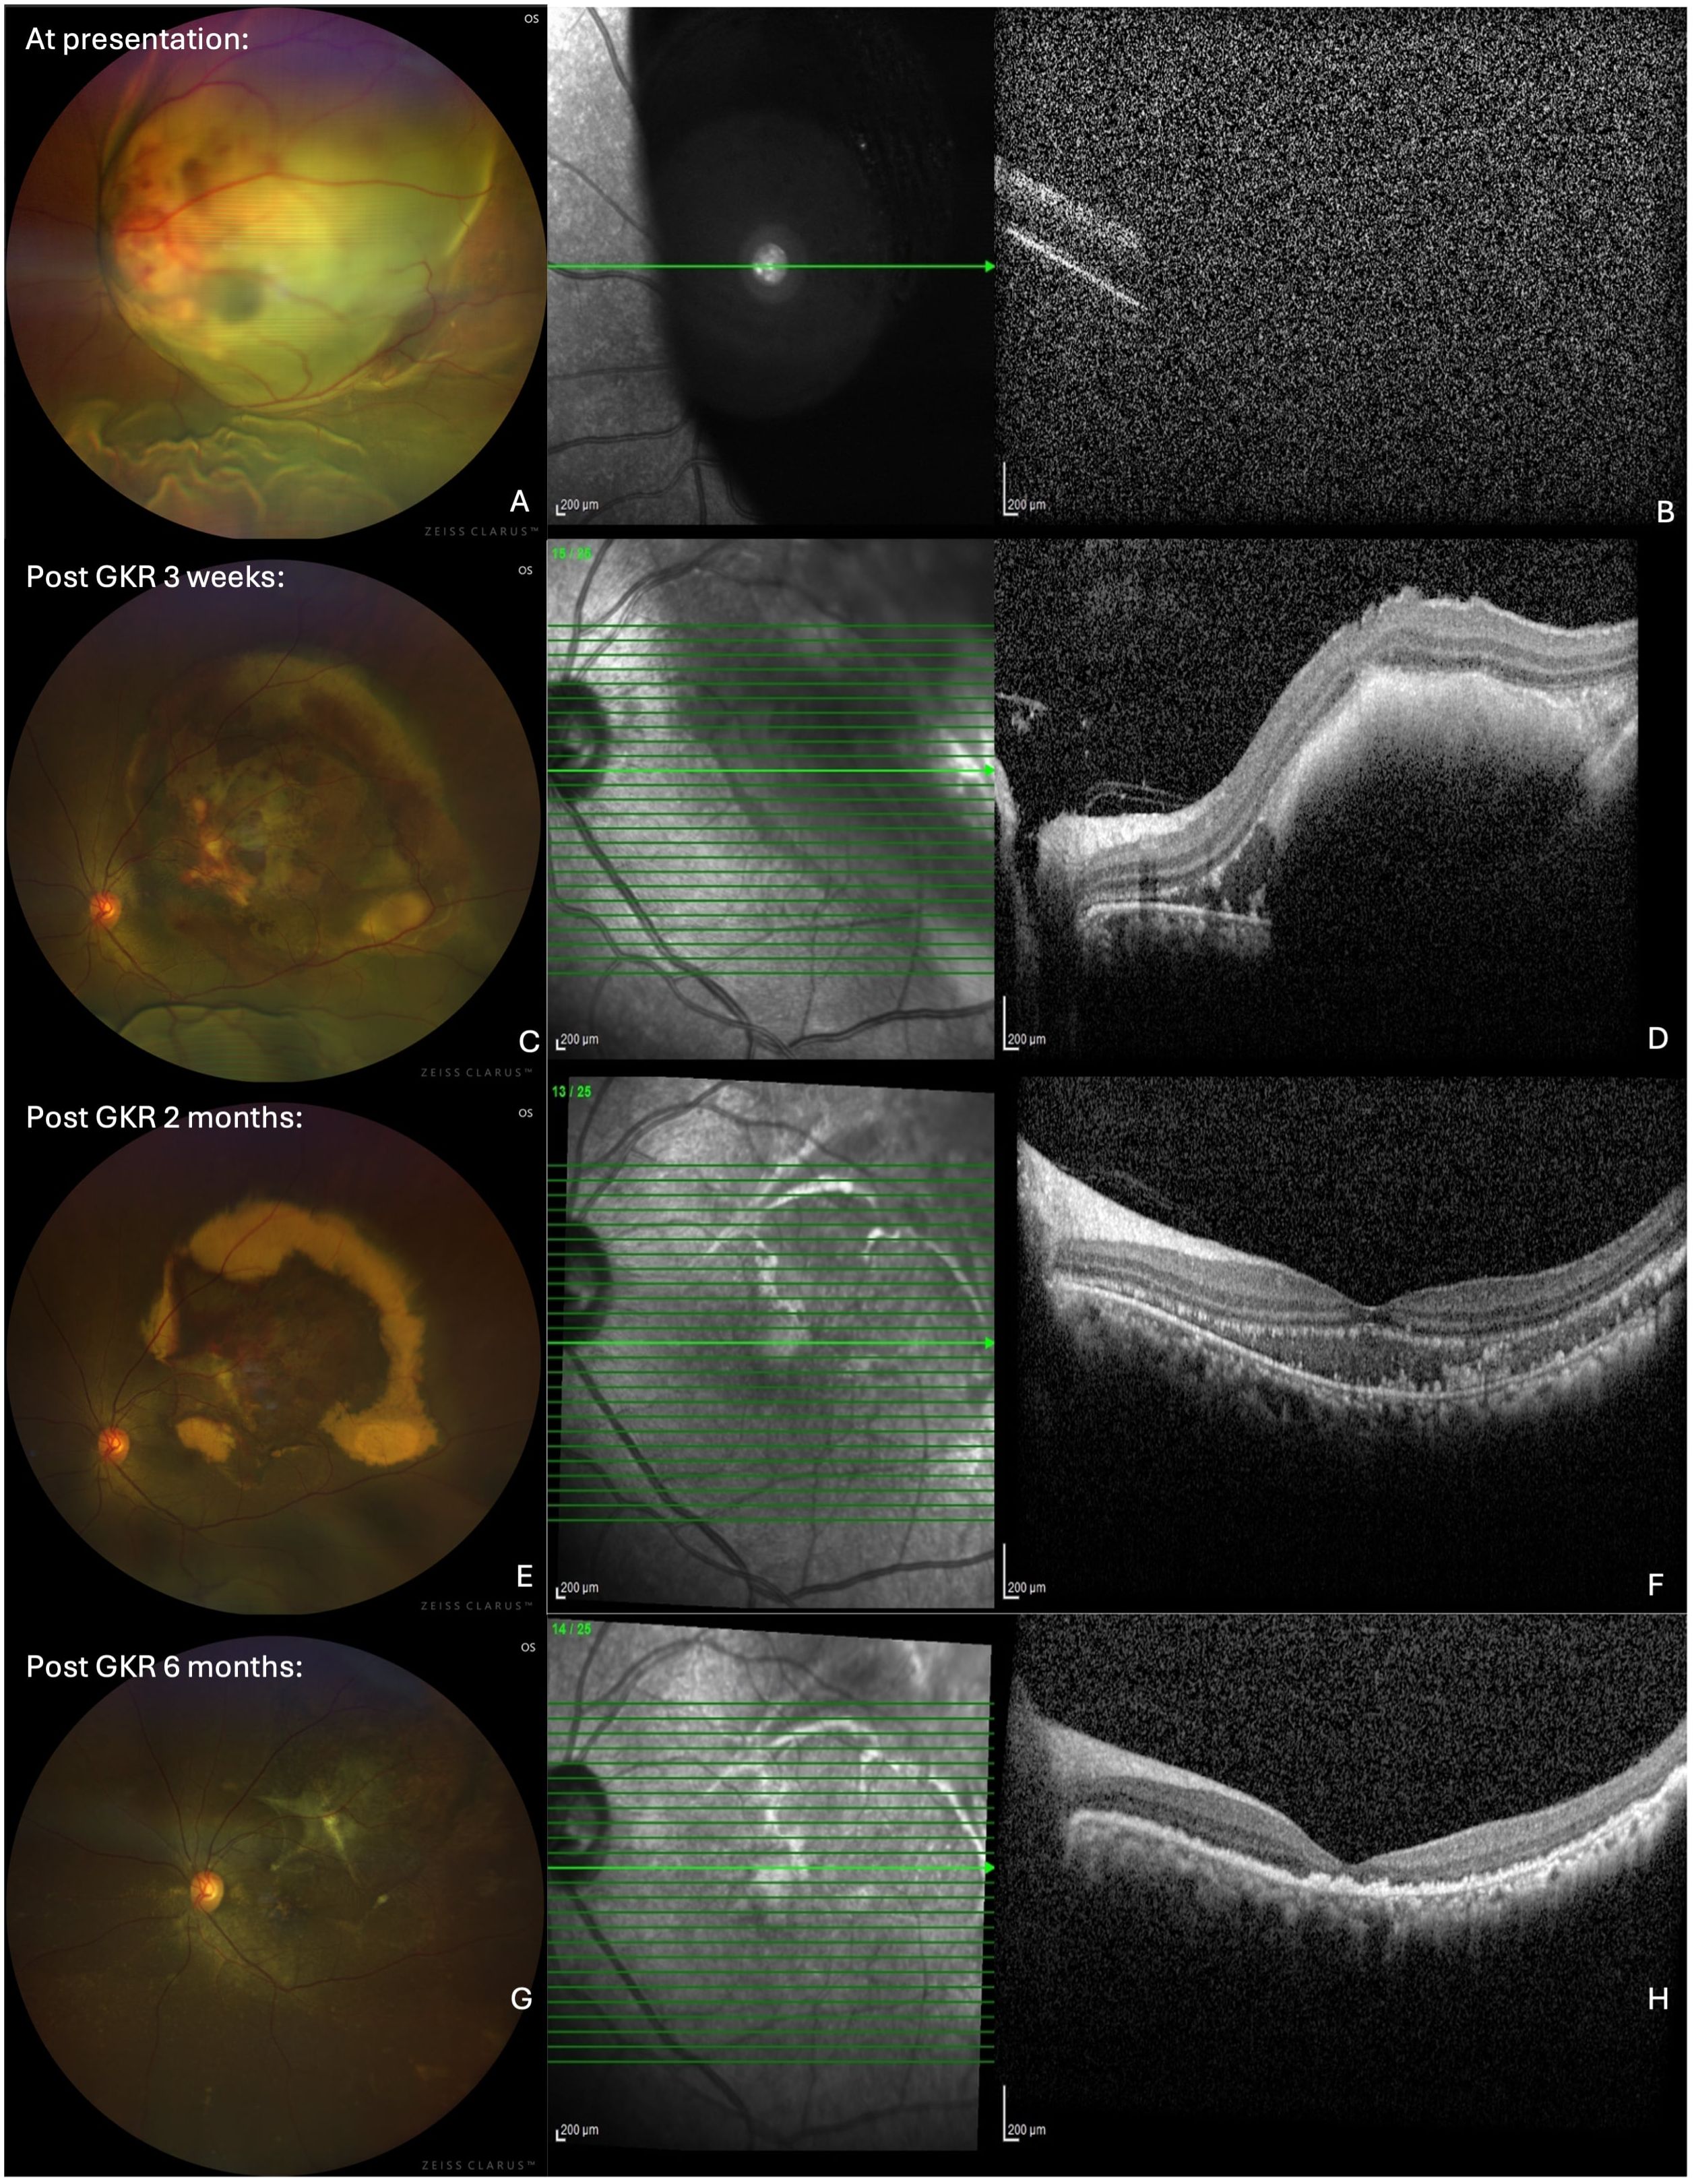

Introduction: Choroidal metastasis generally has poor prognosis and are most commonly originated from breast carcinomas.1,2 While systemic chemotherapy offers therapeutic benefits, local therapies are often necessary for symptom management and tumor control. Gamma Knife Radiosurgery (GKR), originally developed for intracranial lesions, has emerged as a promising treatment for choroidal metastasis, offering high precision and minimized toxicity with fewer ocular side effects compared to conventional radiotherapy. This case report explores the use of GKR in a patient with choroidal and brain metastases from breast carcinoma. Case Presentation: A 44-year-old woman with a history of treated left breast carcinoma presented with 3 months gradual vision loss in her left eye. Her visual acuity at presentation was Counting Fingers (CF). Imaging revealed a choroidal metastasis along with multiple brain metastases. The patient underwent GKR for both choroidal and intracranial metastases, receiving doses ranging from 16-18 Gy at 50-90% isodose. Following treatment, significant tumor regression was observed, with marked reduction in retinal detachment and vision improvement to 6/18. At post-GKR 6 months, both the choroidal mass and retinal detachment had fully resolved, but her visual acuity remained limited due to fovea atrophy. Conclusion: This case demonstrates GKR's potential as a non-invasive and effective modality for simultaneous treatment of choroidal and intracranial metastases. In palliative settings, especially for patients with limited life expectancy, GKR can provide symptomatic relief and improved life quality with minimal invasiveness, which is particularly valuable for younger patients facing advanced metastatic cancer. The importance of a multidisciplinary approach in managing complex metastatic disease is also highlighted. Future studies are warranted to fully define the role of GKR in choroidal metastasis and its long-term sequelae.